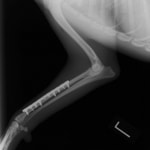

症例3:キルシュナーワイヤーのピンニングによる整復

ペルシャ猫 11ヶ月齢 雄

他院にて左大腿骨遠位の成長板骨折(salter-harrisⅠ型)が認められており、治療相談を目的として来院。当院にて、キルシュナーワイヤーを用いたピンニングにより骨折部位の整復を行いました。術後の経過は良好で、現在も経過観察中です。

術後レントゲン

Arthrex社のターゲティングデバイスを用いてピンニングの位置を調整することで、確実な固定を行っています。当院ではこの手術器具以外にも、人の手術にも使用される様々な器具を導入し、手術精度を高め、また医療メーカーと新しい器具の開発、試作にも取り組んでおります。